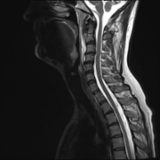

Acute calcific deposit on the enthesis of the longus colli muscle

The severe cervical spine pain prompted an emergency MRI examination, which showed a clear prevertebral inflammatory soft tissue process. On close inspection, a calcific deposit anterior to the dens axis can already be suspected on MRI (especially T2 or axial T1fs Gd+). The calcium depot is only shown very fluffy on X-ray and CT, suggesting an acute stage with precipitation/resorption of the calcific milk.

Therapy is initially conservative. Punctures and surgery of the calcific deposit can be done from endooral.

The longus colli muscle is a less common location of this condition, which should be referred to as HADD or acute calcific deposit. Also affected may be supraspinatus tendon and other tendons of the rotator cuff, extensor carpi radialis tendon, deltoid muscle, or hip adductors.